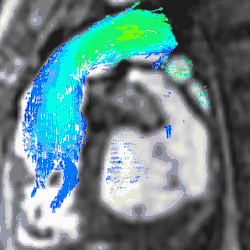

Conventional phase contrast imaging can be extended by applying flow-sensitive gradients in 3 orthogonal planes within a 3D volume throughout the cardiac cycle. Such 4D imaging encodes the velocity of flowing blood at each voxel in the volume enabling fluid dynamics to be visualised using specialist software. Applications are in complex congenital heart disease and for research into cardiovascular flow characteristics - however it is not in routine clinical use due to the complexity of post-processing and relatively long acquisition times.[26]

4D flow models. Intra- and extracardiac flow is visualised in a time-resolved 4D volume encompassing the heart and great vessels. Left: Flow velocity. Centre: Streamlines. Right: Flow vectors.